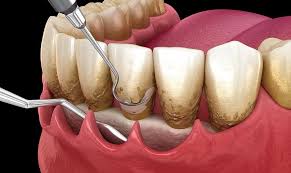

Pathologie parodontale S3

4 examensExamens disponibles

Patho paro S3 #1

Patho paro S3 #2

Patho paro S3 #3

Patho paro S3 #4

Thérapeutiques parodontales étiologiques

2 examensExamens disponibles

QCM paro #1

QCM paro #2

Thérapeutiques parodontales

3 examensExamens disponibles

Thérapeutiques paro #1

Thérapeutiques paro #2

Thérapeutiques parodontales #3